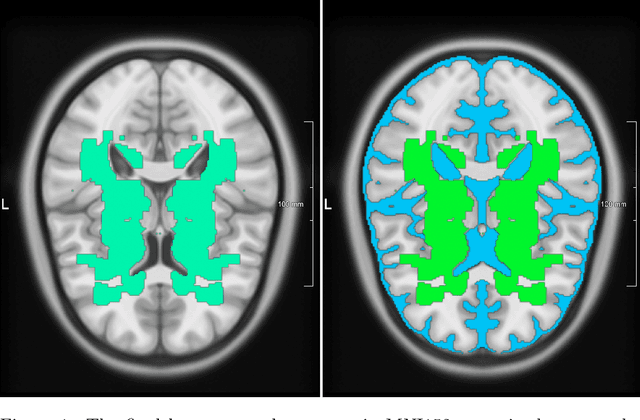

Lacunes of presumed vascular origin are fluid-filled cavities of between 3 - 15 mm in diameter, visible on T1 and FLAIR brain MRI. Quantification of lacunes relies on manual annotation or semi-automatic / interactive approaches; and almost no automatic methods exist for this task. In this work, we present a two-stage approach to segment lacunes of presumed vascular origin: (1) detection with Mask R-CNN followed by (2) segmentation with a U-Net CNN. Data originates from Task 3 of the "Where is VALDO?" challenge and consists of 40 training subjects. We report the mean DICE on the training set of 0.83 and on the validation set of 0.84. Source code is available at: https://github.com/hjkuijf/MixLacune . The docker container hjkuijf/mixlacune can be pulled from https://hub.docker.com/r/hjkuijf/mixlacune .